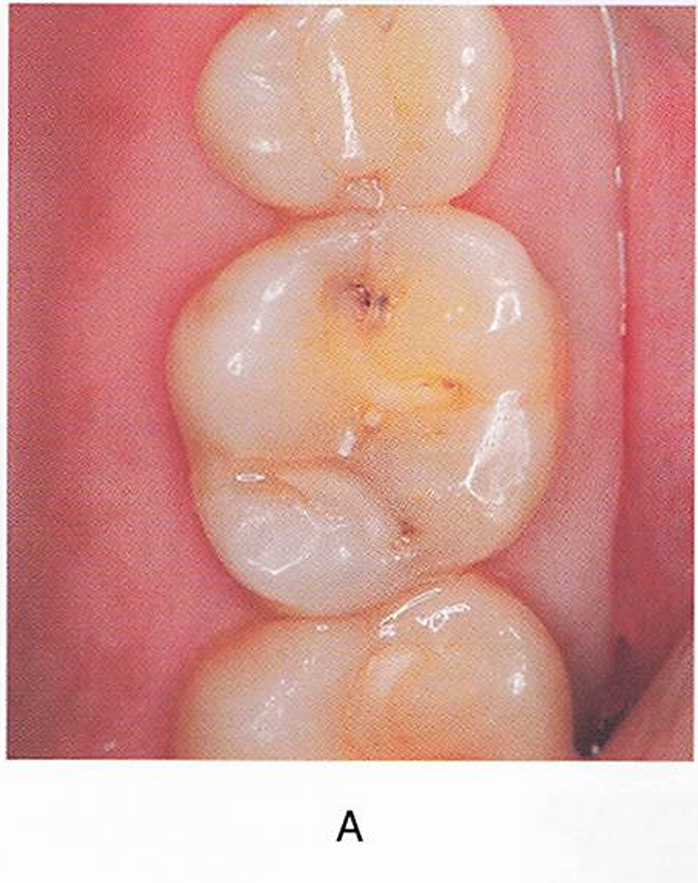

午後-95

60歳の男性。上顎左側第一大臼歯が水にしみることを主訴として来院した。10年前に修復処置を受けたという。コンポジットレジン修復を行うことになった。初診時の口腔内写真(A)、エックス線画像(B)および回転切削器具の写真を別に示す。 最初に使用するのはどれか。1つ選べ。

a. ①

b. ②

c. ③

d. ④

解答を見る

a